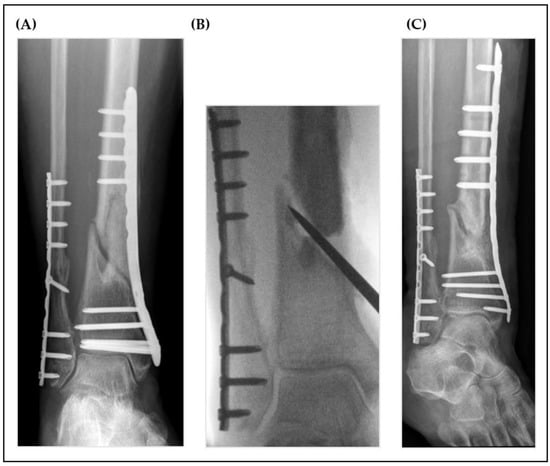

1. Introduction

2. Material and Methods

2.3. Surgical Technique